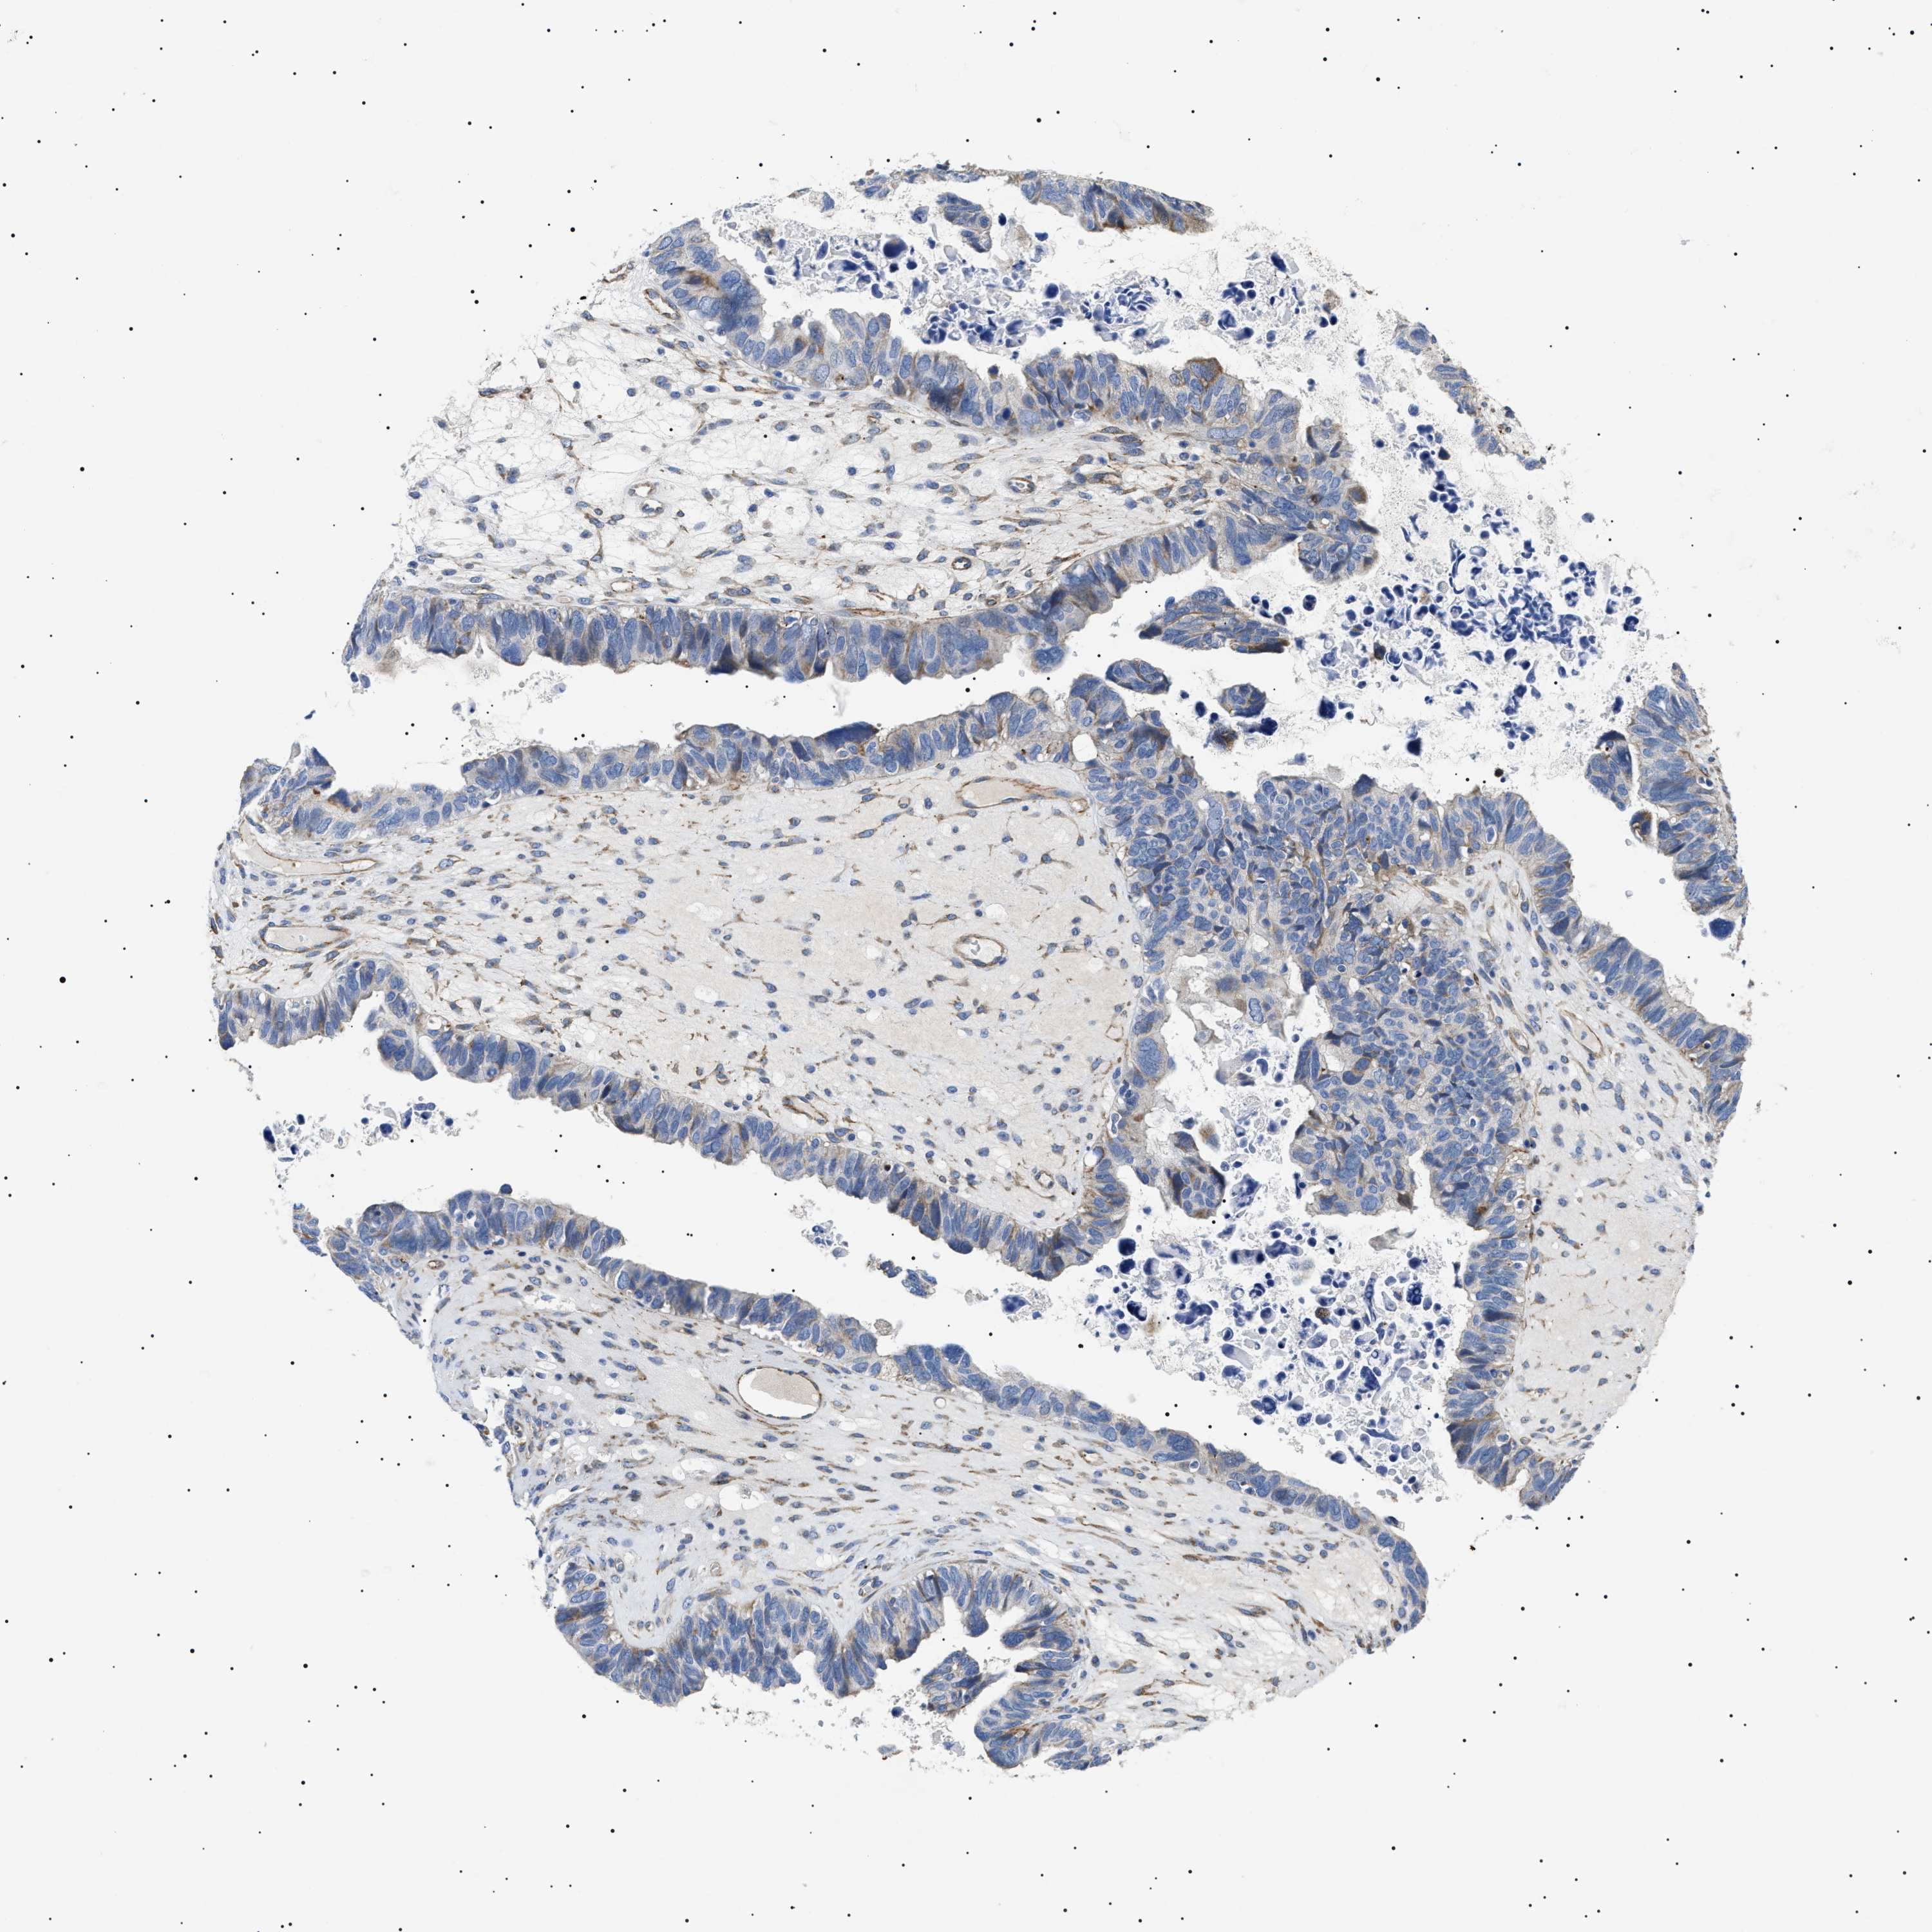

OVARIAN CANCER - Protein expressioni

A mouse-over function shows sample information and annotation data. Click on an image to view it in a full screen mode. Samples can be filtered based on level of antibody staining by selecting one or several of the following categories: high, medium, low and not detected. The assay and annotation is described here.

Note that samples used for immunohistochemistry by the Human Protein Atlas do not correspond to samples in the TCGA dataset.

Antibody stainingi

Antibody staining in the annotated cell types in the current human tissue is reported as not detected, low, medium, or high, based on conventional immunohistochemistry profiling in selected tissues. This score is based on the combination of the staining intensity and fraction of stained cells.

Each image is clickable and will lead to virtual microscopy that enables deeper exploration of all samples and also displays staining intensity scores, fraction scores and subcellular localization as well as patient and tissue information for each sample.

Antibody HPA016579

Antibody HPA059374

Cystadenocarcinoma, serous, NOS

Carcinoma, endometroid

Cystadenocarcinoma, mucinous, NOS

Carcinoma, NOS